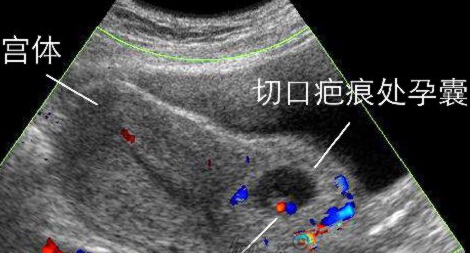

(一)孕早期 怀孕12周内为孕早期。此时间段出血多见于宫内孕自然流产,“先兆流产”这个诊断大家应该并不陌生;再者“宫外孕”阴道出血也不少见;还有一种特殊部位的妊娠不能轻忽——瘢痕妊娠。随着剖宫产率的上升,瘢痕妊娠在临床上的发病率也呈逐渐上升趋势。

近年来发病率呈逐渐上升趋势的“瘢痕妊娠”是指有剖宫产史的孕妇,胚胎着床于子宫下段剖宫产切口瘢痕处,为剖宫产远期并发症之一。主要特点是停经后不规则阴道出血。易被误诊为不全流产而行刮宫术,从而导致致命性大出血。早期明确诊断很重要,经阴道B超是诊断瘢痕妊娠的主要手段。一旦确诊需立即住院治疗,治疗方案依据个体化原则。可以采用化疗药甲氨蝶呤,也可子宫动脉栓塞后行清宫术;也可选择手术切除局部病灶。